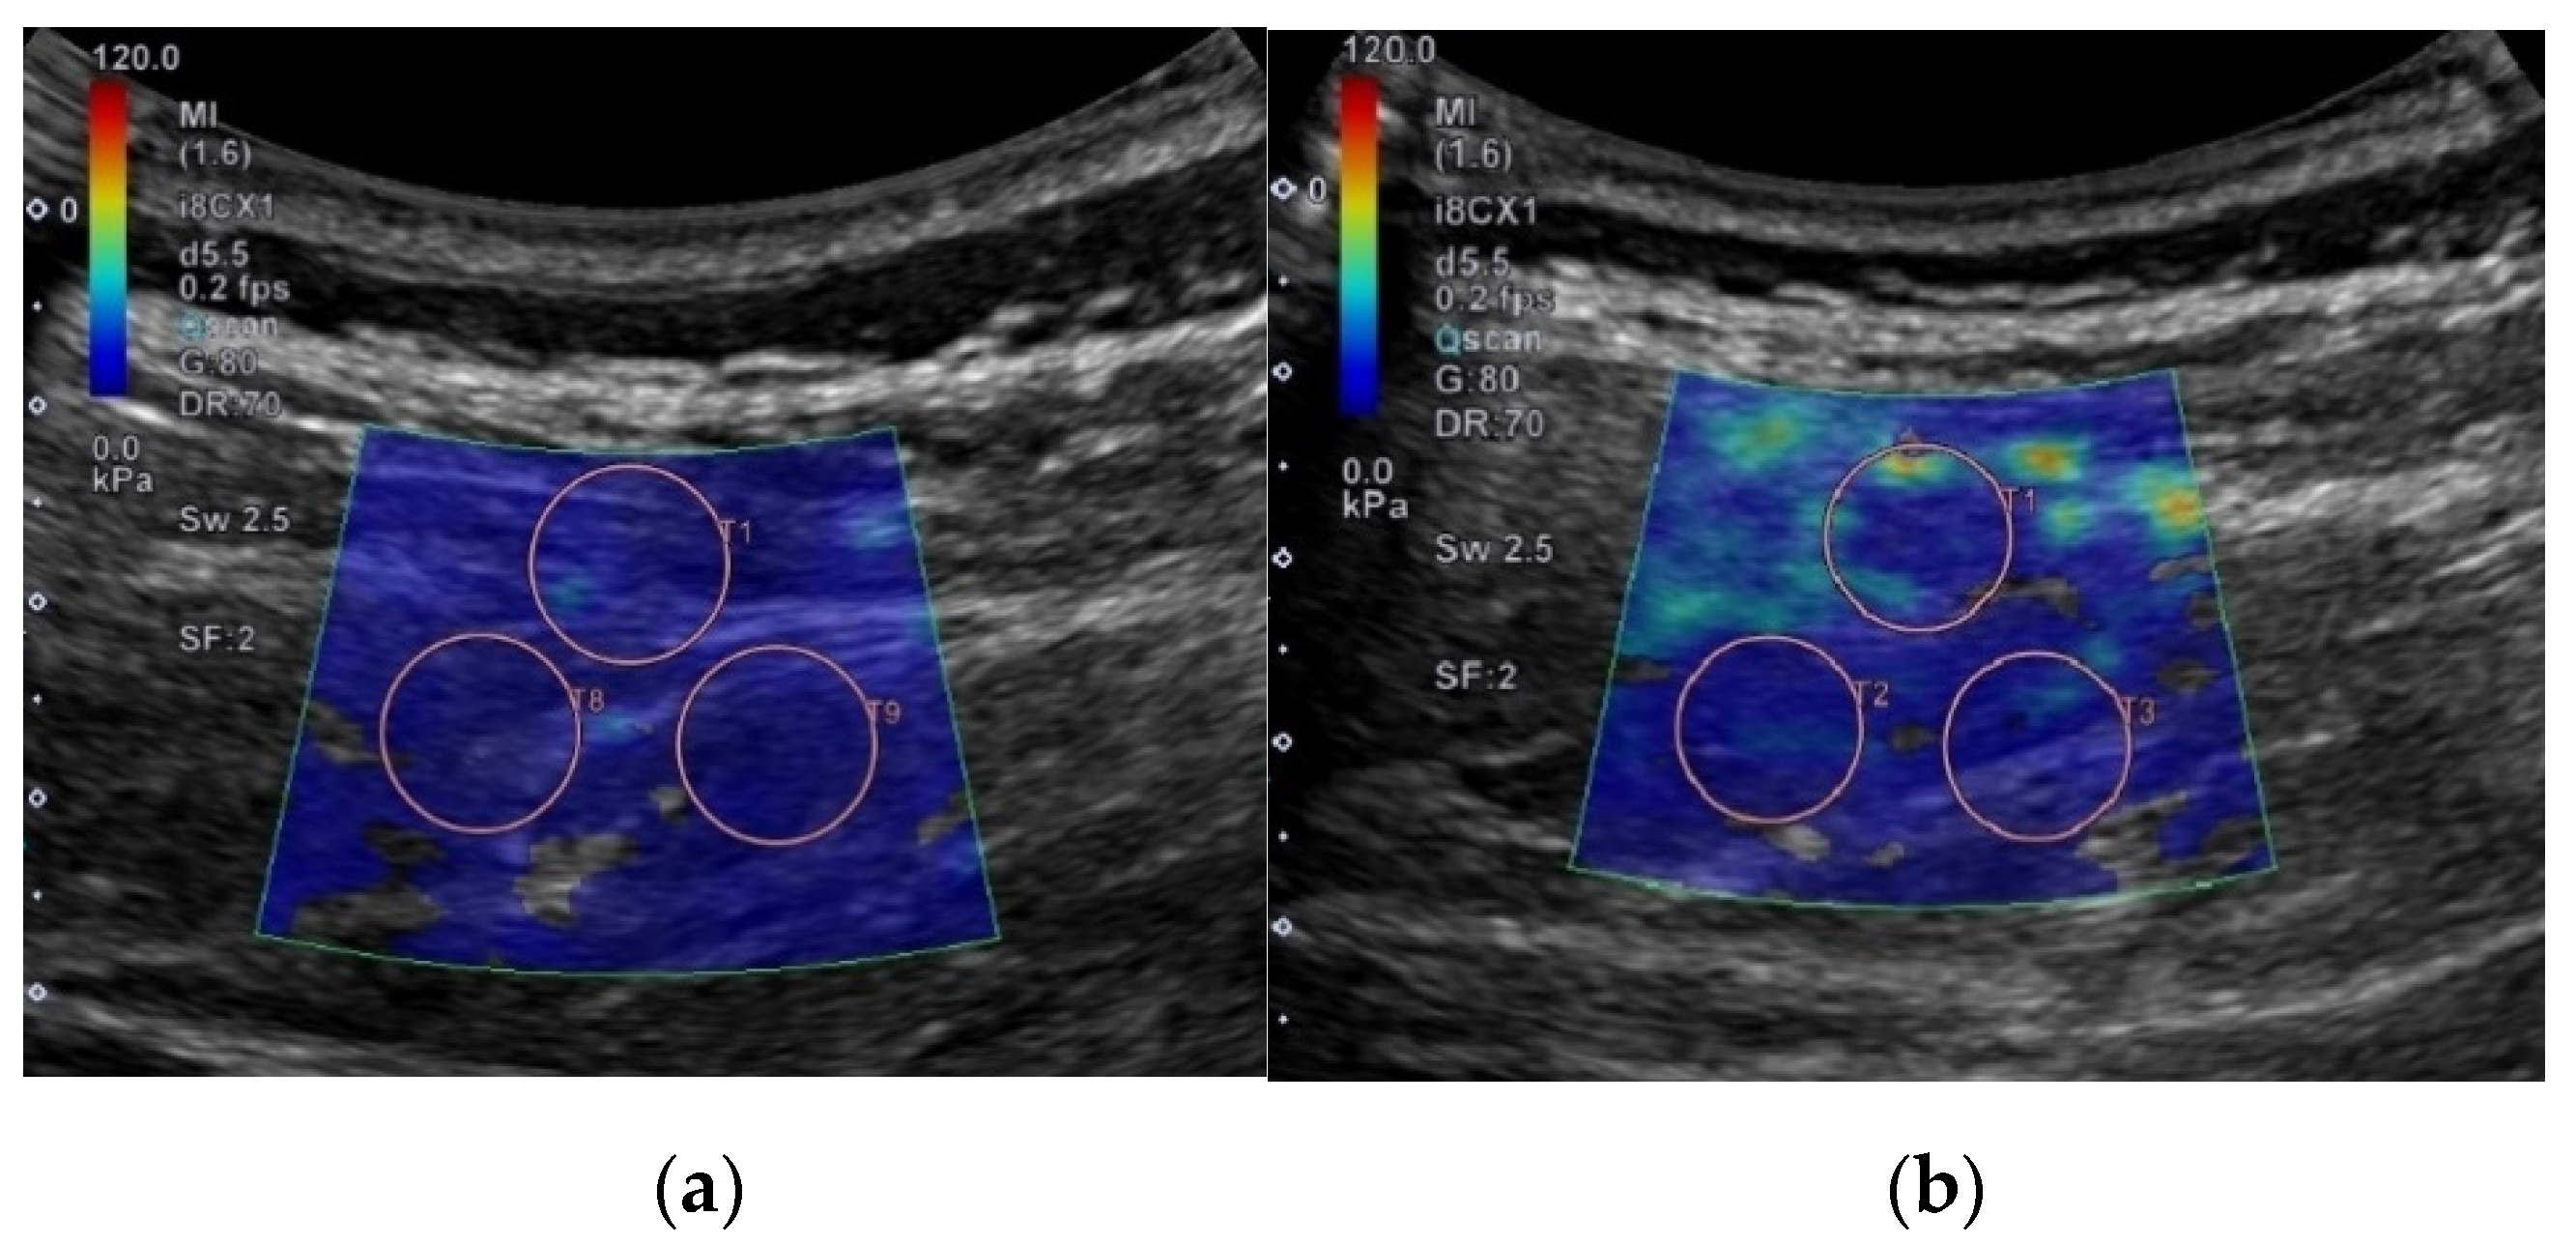

Each shear elastic modulus of the aforementioned muscles was evaluated by measuring shear-wave propagation speed in the tissue, which was generated using SWE at each measurement posture. The circular regions of interest (ROIs) were set in the color-coded boxes on the SWE mode (Figure 3). Three circular ROIs with a diameter of 10 mm were set in the color-coded box, with one located at the top–center of the box and the other two located at the inferior to the first-assigned circular ROI (Figure 3) [21,24]. Shear elastic modulus at the set ROI was automatically calculated from the ultrasound imaging device. The mean shear-elastic-modulus values of the three circular ROIs were calculated for each muscle per posture for five images. ROIs were determined by the same examiner.

Figure 3.

Example for setting regions of interest to measure shear elastic modulus in different postures on flat and Wilson table. In this case, erector spinae 1 located at L3–4 is shown: (a) flat table; (b) Wilson table.